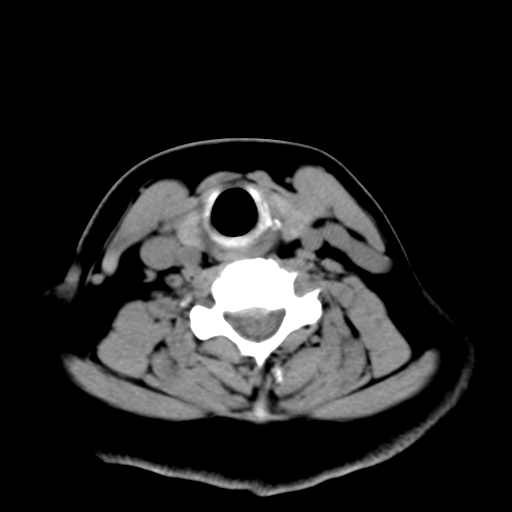

标题: CT25491:女,55岁,发现左侧甲状腺肿块一个月。 [打印本页]

标题: CT25491:女,55岁,发现左侧甲状腺肿块一个月。

女,55岁,发现左侧甲状腺肿块一个月,彩超示:甲状腺多发结节伴左叶结节液化。